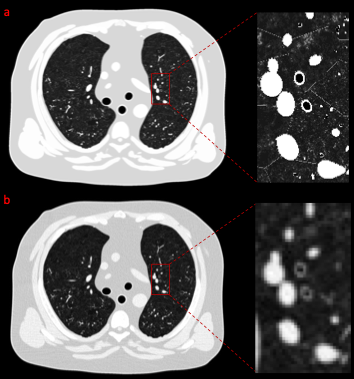

Chronic obstructive pulmonary disease (COPD) is a major cause of death in the US, characterized by emphysema and bronchitis. Bronchitis is the inflammation of the bronchial tubes (airways), and airway measurements using quantitative CT can provide an objective assessment of bronchitis severity. However, the accuracy of this measurement is limited by the spatial resolution and image noise of the CT imaging systems. The emerging photon-counting CT (PCCT) technology has the potential to improve airway quantification due to its superior noise and spatial resolution performance. To quantify its benefits, it is important to do a systematic task-specific evaluation of PCCT against energy-integrating CT (EICT) for airway measurements. However, conducting such studies on real patients is not cost-effective and has ethical limitations as well. Additionally, acquiring ground-truth information from patient images is also not feasible, which is required to measure the degradation caused by the scanner or the imaging parameters. The virtual imaging trial framework can simulate real CT scanning of anthropomorphic-computational human phantoms (XCAT) with varying severity of bronchitis. This framework was used in this study to compare the quantitative performance of deep silicon-based PCCT with conventional EICT for airway measurements and identify the optimal CT imaging parameters for accurate bronchitis quantification.

(b) CT image acquired at 350 mA and reconstructed using weighted filtered back projection and standard kernel.

[W/L] = [1000/-450].